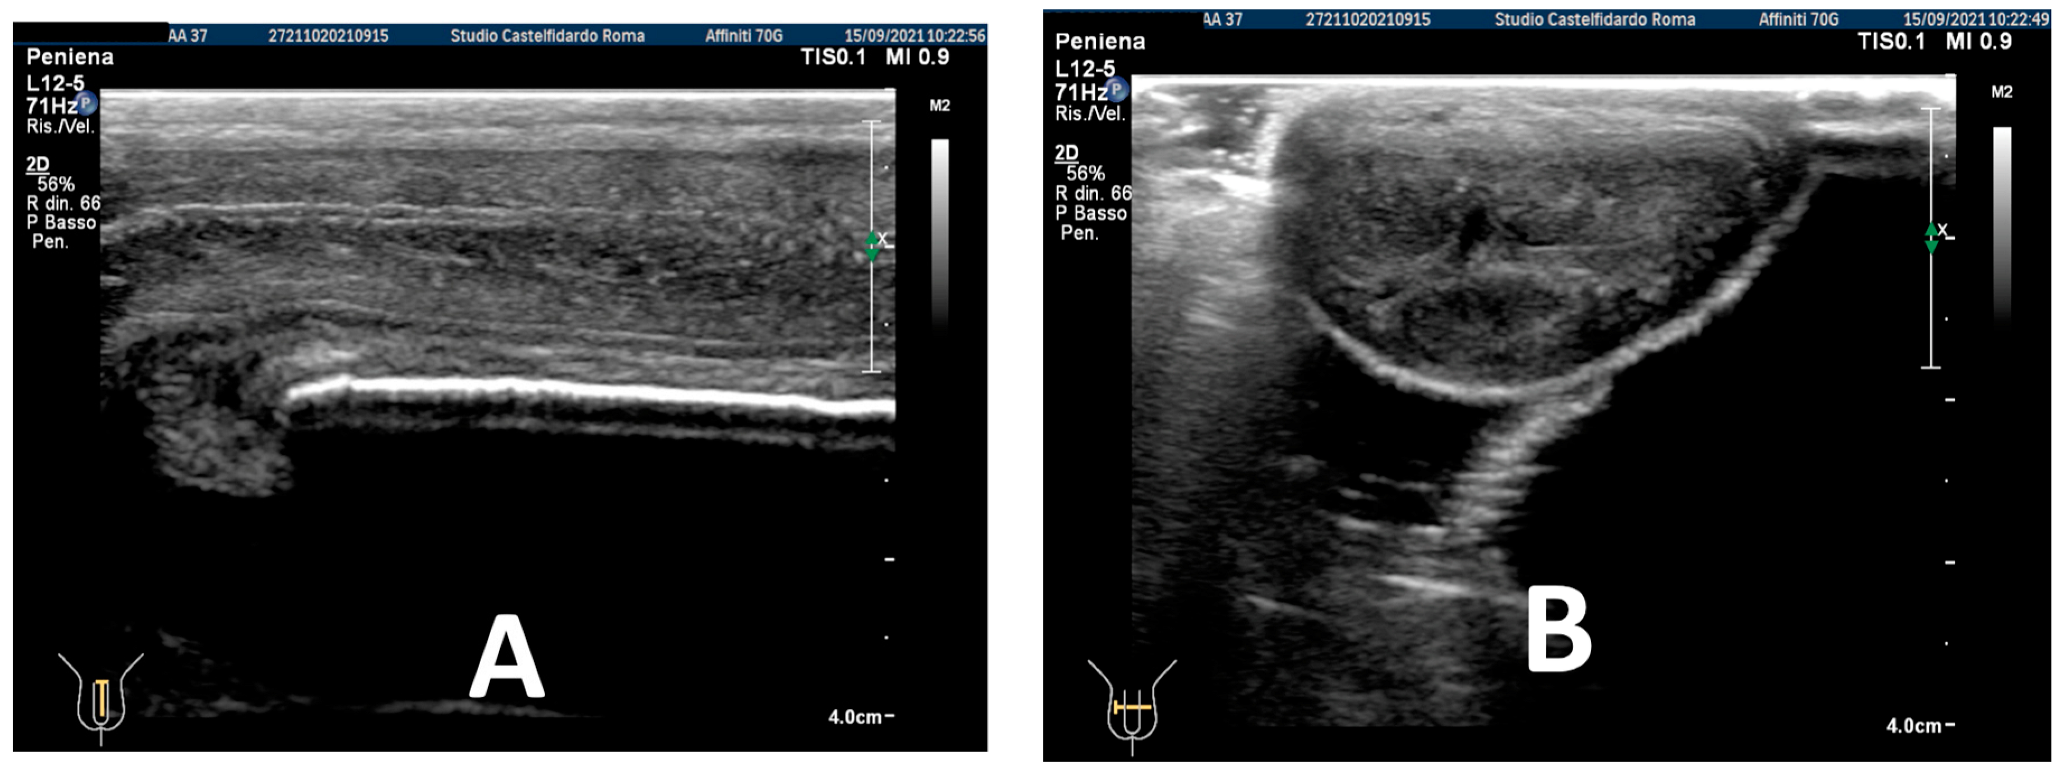

| 3 | 33 years | None | Middle third | (A) 20.6 × 15.2 × 4.42 mm volume = 724 mm3 + some small calcifications, the largest of which measured 1.9 × 4.1 mm | (A) 30-degree dorsal penile curvature | (A) score 2 | (A) score 26 | 3 years and 5 months | orally: Silymarin 400 mg + Ginkgo biloba 250 mg + Propolis 600 mg + Bilberry 160 mg + Vitamin E 800 IU/once a day, for 41 months. + topically: Propolis creme/twice a day/for 41 months. + peri-plaque penile injections: Pentoxifylline 100 mg (30 G needle) every 15 days for 6 months, and then monthly for 12 months, and then 1 injection every other month. for 12 months (total = 30 injections) |

| (B) No plaque detected | (B) None | (B) score 0 (after six months) | (B) score 27 |